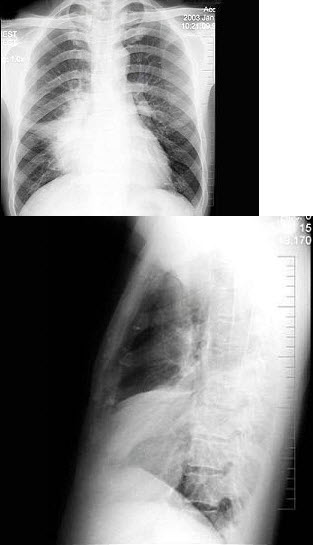

134、单项选择题

男,36岁,胸痛、发热2周余,X线检查如图,最可能的诊断是()

A.右下肺炎症

B.右肺肿瘤

C.右下肺不张

D.右肺中叶综合征

E.右侧气胸

点击查看答案